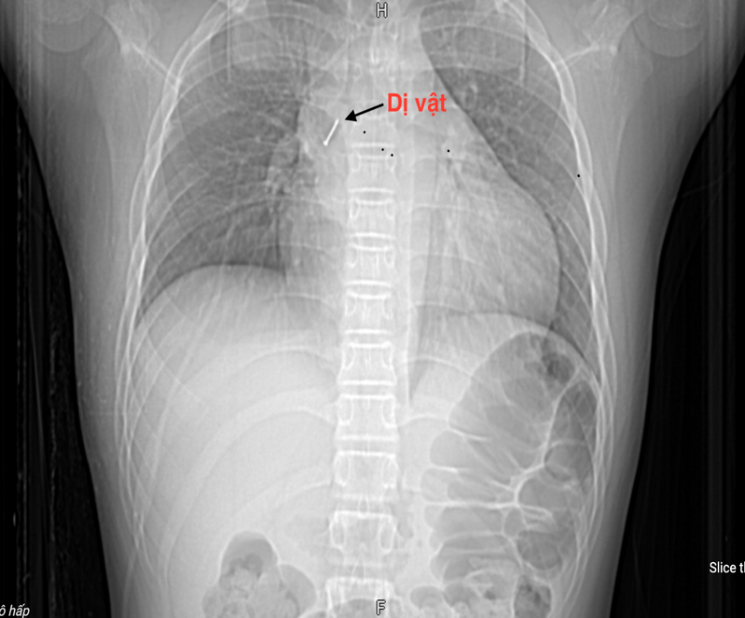

Keluarga itu panik dan membawa kanak-kanak itu ke hospital berhampiran. Di sini, pesakit menjalani ujian darah, imbasan CT dada, dan bronkoskopi fleksibel. Doktor menentukan bahawa objek asing itu berada jauh di dalam bronkus perantaraan kanan. Kerana objek asing itu tajam dan menembusi dinding bronkial, menyebabkan pendarahan dan edema mukosa, mengeluarkannya sangat sukar. Selepas lebih 2 jam pembedahan tidak berjaya, pesakit telah dipindahkan segera ke Hospital Paru-paru Pusat.

Menerima kes itu, Sarjana, Pakar II Doktor Nguyen Le Nhat Minh - Ketua Jabatan Endoskopi Diagnostik dan Intervensi (Hospital Paru-paru Pusat) dan pasukannya dengan pantas melakukan prosedur bronkoskopi fleksibel untuk mengeluarkan objek asing untuk rawatan.

"Objek asing adalah pin tajam, tersangkut di bronkus perantaraan, hujung tajam menembusi jauh ke dalam dinding bronkial. Ini adalah kes yang sangat sukar untuk mengeluarkan objek asing, kerana sebagai tambahan kepada sifat dan ciri-ciri objek asing seperti di atas, pesakit juga bertindak balas secara refleks, jadi ia memerlukan manipulasi yang cepat dan tepat untuk mengelakkan koyaknya dinding bronkial, yang boleh menyebabkan dinding bronkial menjadi lebih dalam, yang boleh menyebabkan objek asing menjadi lebih dalam, yang boleh menyebabkan objek asing menjadi lebih dalam, atau mendorong objek asing menjadi lebih dalam. pneumothorax, dan pneumomediastinum.

Komplikasi ini malah boleh menyebabkan kegagalan pernafasan akut bagi pesakit. Oleh itu, selepas penilaian menyeluruh, pasukan dengan berhati-hati mengeluarkan kepala paku yang tertanam di dinding bronkial ke keadaan bebas menggunakan forsep bronkoskopi khusus, kemudian perlahan-lahan dan berjaya mengeluarkan objek asing itu. Proses itu berlaku dalam masa 15 minit,” kata Dr. Minh.